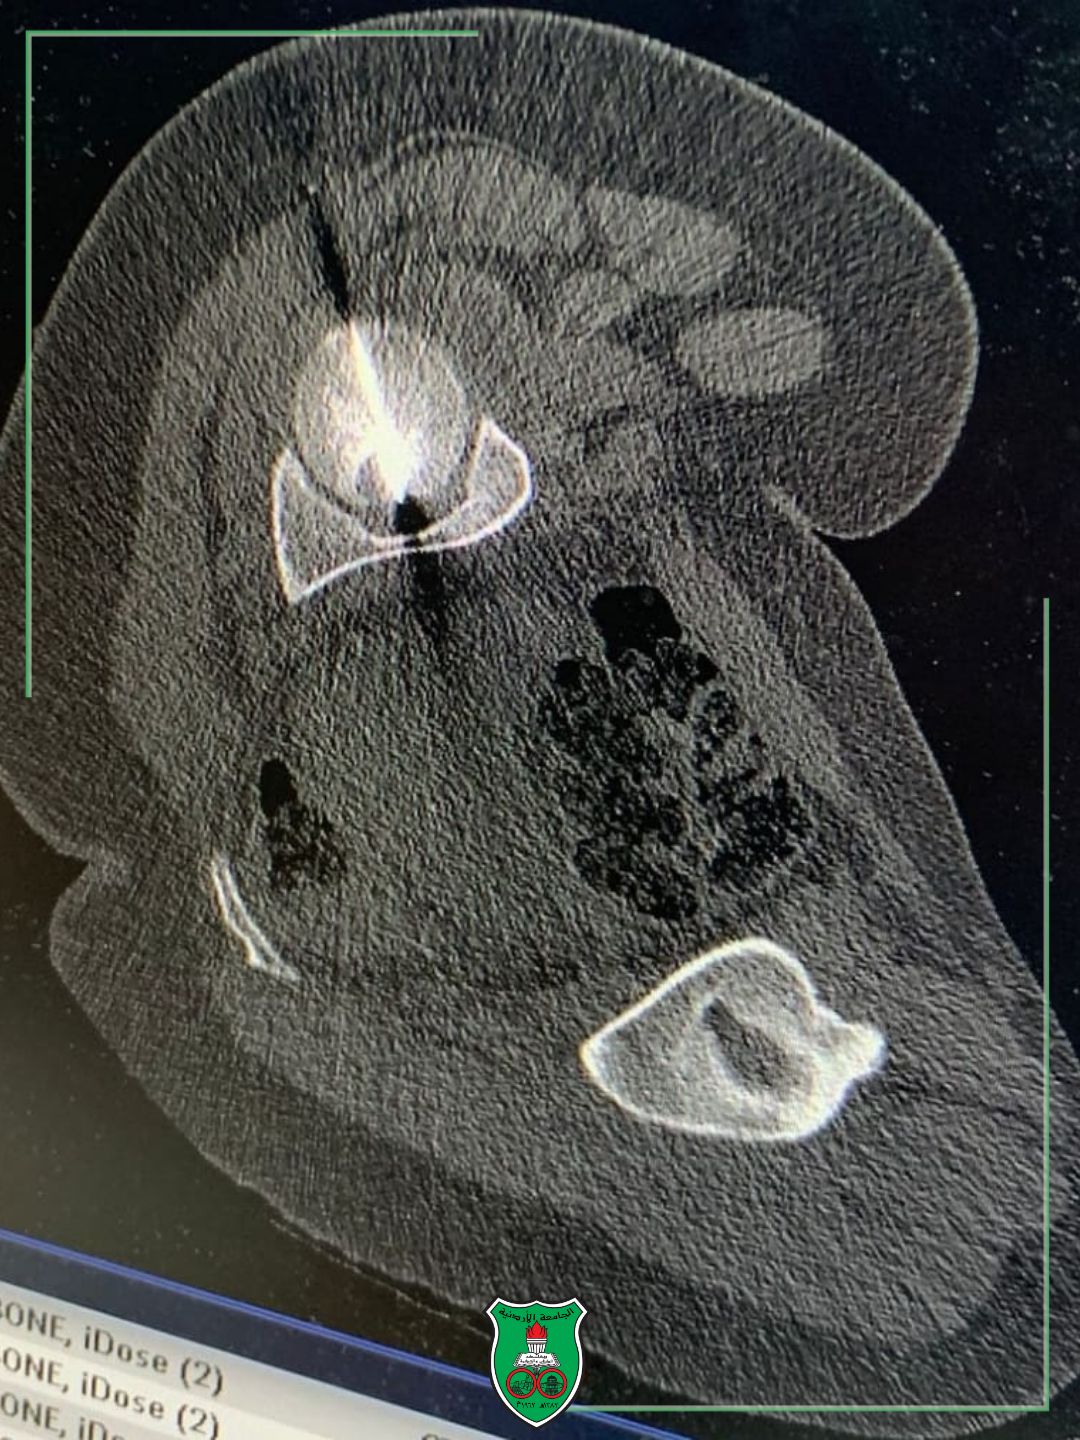

وأوضح البطوش أنَّ الفريق الطبيّ تمكّن من الوصول إلى الورم بدقة عالية باستخدام التصوير الطبقيّ المحوريّ (CT Scan)، قبل إجراء الكيّ الحراريّ عبر تقنية المايكروويف (Microwave Ablation)، وهي إحدى أحدث التقنيات العالميّة لعلاج أورام العظام دون اللجوء للجراحة المفتوحة.